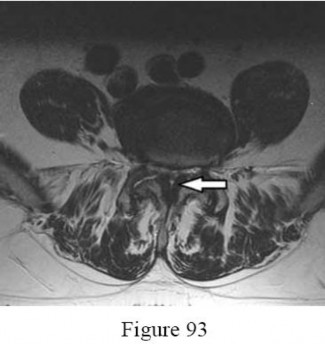

Question 23

A 55-year-old male with a long-standing history of ankylosing spondylitis presents to the emergency department with severe back pain after a ground-level fall.

A CT scan demonstrates a fracture through the T8-T9 intervertebral disc space extending into the posterior elements. He is neurologically intact. What is the most appropriate management?